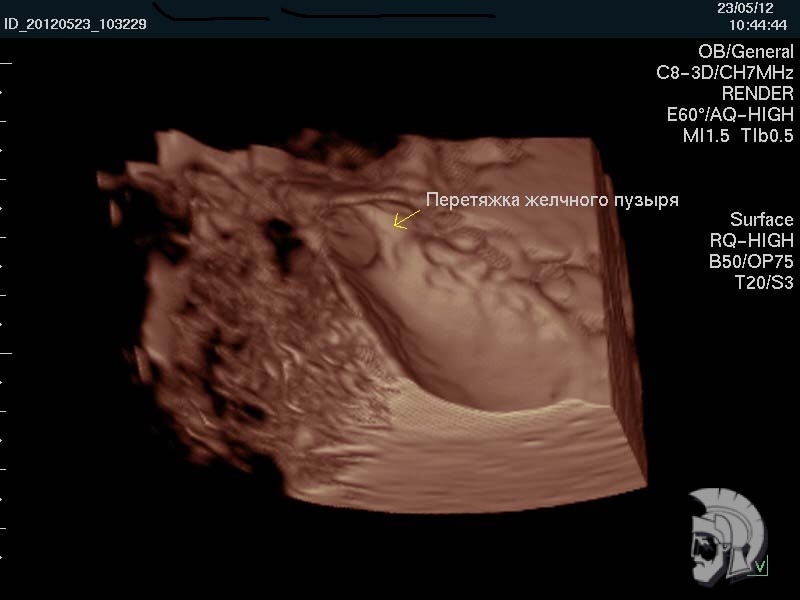

| 3D-фото желчного пузыря. Тот же случай |

| Фото желчного пузыря. Перетяжка в нижней трети желчного пузыря мужчины 43 лет |

Обратите внимание на совершенное качество фотографий, свидетельствующих об экспертном классе наших аппаратов УЗИ!

Использование ультразвуковых аппаратов экспертного класса с режимами энергетического ДОППЛЕРа и цветового допплера позволяет врачам Курортной клиники мужского здоровья выявлять патологические изменения на ранних этапах.